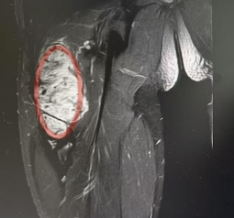

术前影像:红色标记部分为侵袭性纤维瘤

“患者入院后MR检查提示恶性肿瘤可能,肿块约10*2*2CM大小,经B超引导下行穿刺活检,病理提示:侵袭性纤维瘤病。”据长沙市中心医院手足显微外科副主任医师曾驰介绍,由于肿块较大,无法保守治疗,在完善术前准备后行瘤体切除术,手术顺利,术后患者恢复良好。